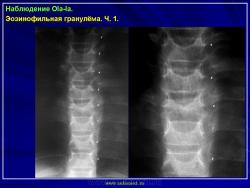

Из опубликованных наблюдений н сайте.